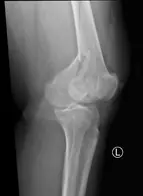

Fracture de l’extremite inferieure du femur